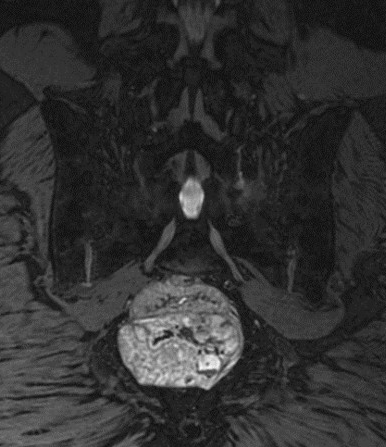

入院后,脊柱与骨肿瘤病区王栋主任牵头,赵波副主任医师、郭帅主治医师团队仔细检查,全面评估。超声穿刺活检提示脊索瘤(经典型),影像检查提示肿瘤位于第3、4骶椎,大小约6.2cm×6.7cm×6.4cm,突入盆腔压迫直肠,近端第2骶椎部分骨质已破坏,侵犯双侧骶2及以远神经根。

手术当日,在麻醉科张珍妮医生团队的生命保障下,王栋主任主刀,赵波副主任医师、郭帅主治医师作为助手,借助术中导航系统实时引导,精准分离肿瘤与周围组织;严格按照R0切除标准完成肿瘤整块切除,术后病理报告确认切缘阴性,从根源上降低复发风险(文献报道广泛性切除的局部复发率为5%-17%,病灶内切除或边缘性切除的局部复发率为71%-81%);术中黄亚娟、孙丽君技师采用神经电生理监测技术持续追踪骶1神经根功能,使手术成功保留双侧骶1神经根,为术后行走功能保留奠定基础;术后应用VSD装置覆盖切口,有效引流渗液、促进肉芽组织生长,为伤口愈合提供保障,后期拆除VSD装置后见切口愈合良好,无感染事件发生(文献报道此类手术切口感染的发生率在20%-60%)。整个手术历时5小时,术中出血2400毫升,远优于同类手术平均水平(文献报道此类手术出血量在2000-20000毫升,平均7000毫升)。杨先生的术后恢复,也离不开李珂护士长、陈静副护士长、病区护理团队和康复科张司铎医生团队的专业指导。术后泌尿外科薛力主任团队、陈琦副主任医师团队、普通外科张心武副主任医师团队也为杨先生制定了留置导尿、膀胱造瘘/肠造口等序列治疗方案,确保术后大小便功能平稳过渡。